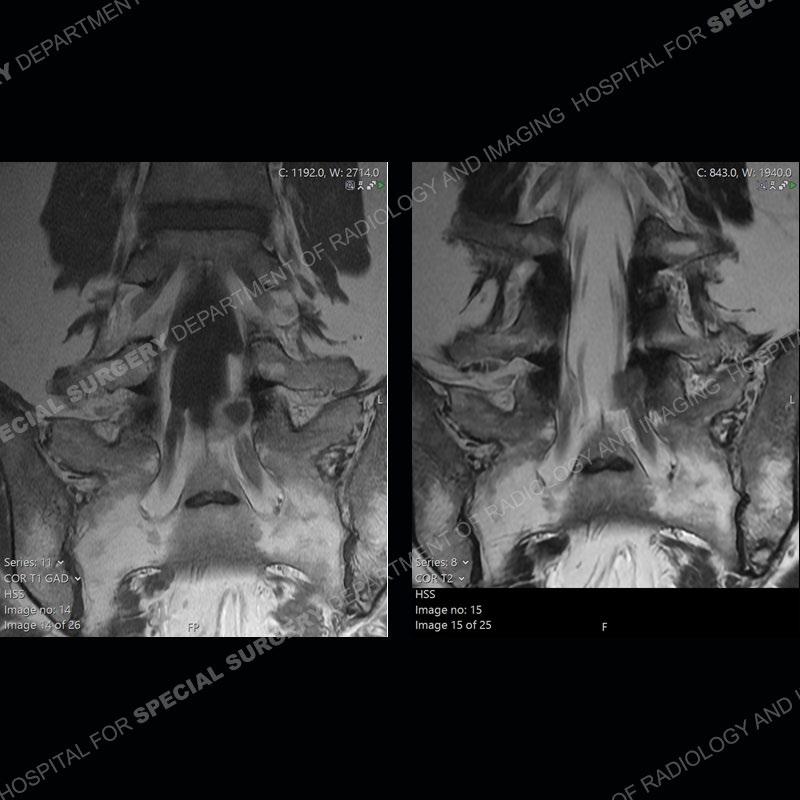

Post operative changes are seen on the left side at L5-S1 where there is near complete removal of the left sided L5 lamina, partial resection of the left L5-S1 facet joint, and resection of the left sided ligamentum flavum. In the anterolateral epidural space about the subarticular recess is a mass that demonstrates similar T1 and T2 signal characteristics to the adjacent degenerated disc. There is enhancement about the periphery of the mass, but the majority of this somewhat geographic or polyploid mass demonstrates no enhancement. The mass exerts prominent mass effect on the left S1 axillary sleeve/proximal nerve root. The left S1 nerve root shows enlargement and increased enhancement as compared to the contralateral right side.

Not as much of a diagnostic dilemma as some other cases but more so just a very nice example of what can be a difficult assessment at times. The evaluation of granulation tissue/scar/epidural fibrosis vs. disc herniation particularly in the earlier post operative period can be very difficult. Clues that can assist in identifying a disc herniation are a more geographic or polypoid nature to the mass, signal characteristics similar to the adjacent degenerated disc, mass effect upon the thecal sac/adjacent neural structures, and a typical enhancement pattern. As the disc material is avascular, as long as imaging is performed in a relatively rapid fashion after contrast administration (within 20-30 minutes), the granulation tissue around the disc will enhance but the disc material itself will not. If there is a marked delay between contrast administration and imaging, there may be diffusion of contrast into the disc making the assessment very difficult. The marked utility of contrast to help delineate disc vs. scar has led to our institution employing contrast fairly uniformly within the first two years following surgery.

The scar tissue in the setting of prior disc removal will be present in the anterior and anteriorlateral aspect of the epidural space. The signal characteristics can be somewhat variable from slightly more T2 hyperintense earlier on to T2 hypointense as the scar matures. However, the signal does not tend to follow the adjacent degenerated disc. The scar can produce mass effect, but it does not have to do so. In addition, at times the scar may be associated with a retraction of the adjacent thecal sac. Given the vascular nature of the scar there is typically somewhat avid, uniform enhancement which occurs fairly rapidly after contrast administration and begins to diminish within 20 minutes or so. Trying to discern the difference between scar and disc is of paramount importance given the rather poor outcomes associated with resection of scar as compared to disc material.